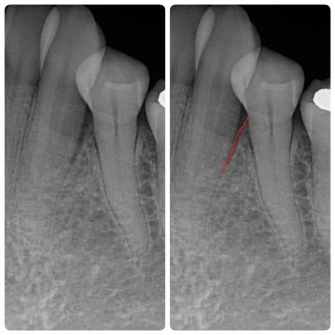

◎歯周組織の再生を促す薬剤「リグロス(保険適応)」を使って歯周組織が再生された一例

☆左写真 歯周組織再生療法前 歯槽骨が吸収しています(赤い線)

☆右写真 歯周組織再生療法後 2年半後 歯周ポケット改善 歯周組織改善傾向

歯周病によって破壊された歯槽骨(歯を支える骨)は、自然に元の状態に戻ることはありません。しかし、再生療法を行うことで、骨を元のように戻せる可能性があります。当院では「リグロス(保険適応)」という薬剤を使用した再生療法を行うことができます。リグロスには、歯周組織の再生に必要な細胞の増殖を促進する「b F G F」というタンパク質が含まれています。この成分が、歯周病によって破壊された歯槽骨や歯根膜(歯と歯槽骨を結ぶ組織)を再生させます。